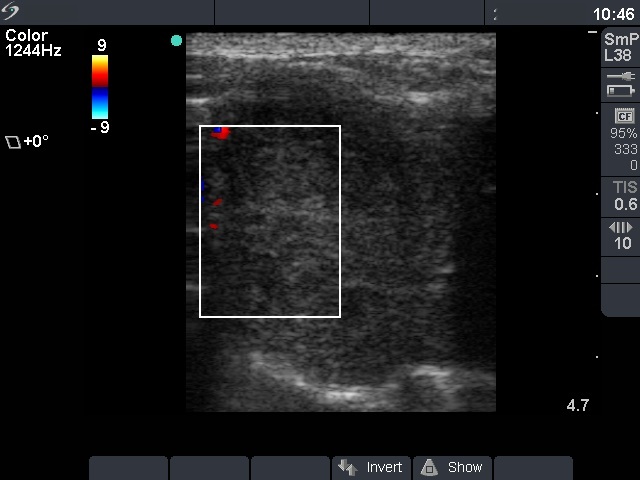

Ultrasonography. There was a large hypoechogenic nodule with irregular borders in the right thyroid. The vascularization was decreased.